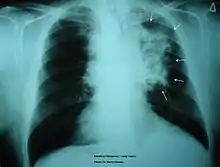

The morbidity of cigarette smoking is nearly 50% with 7 million first-hand smokers and 1.2 millions second hand smokers killed each year[8]. Regardless of active or passive smokers, macrophage accumulation is found in the lungs.[3][5] The diagnostic methods for smoke-related diseases include bronchoalveolar lavage which can also be used for examining smoker's macrophages in addition to augmented inflammatory cells in the alveolar lumen.[1]

The immune functions in smoker’s macrophages are compromised, so the airway pathogens are more likely to accumulate and cause infection.[17] Smoker’s macrophages have reduced expression of HLA-DR antigens, causing immunosuppression.[18][19] In addition, nicotine impairs the phagocytosis of M. tuberculosis and also induces immunosuppression via the activation of alpha-7 nicotinic receptors.[4][17] Meanwhile, due to the impaired TLR2 and TLR4 signaling, macrophages fail to recognize pathogens, so there is a decrease in pathogen clearance.[17] Therefore, smokers are prone to acute respiratory tract infection and community acquired pneumonia.[20]

Chronic Obstructive Pulmonary Disease

Smoking is found to be the most important causative factor leading to COPD.[23] Because of the altered inflammatory response of the macrophages, smoking induces inflammation across the entire airway, which in turns obstructs the airflow. Symptoms of COPD include persistent coughing, wheezing, chest infections and breathlessness. Treatments for COPD usually focus on the source of the problem, which is smoking, thus the general treatment is going through smoking rehabilitation which including nicotine replacement therapy, mental therapy for advice, and support to quit smoking. In certain urgent cases, direct constriction also occurs, in which bronchodilators allow the airway to dilate.